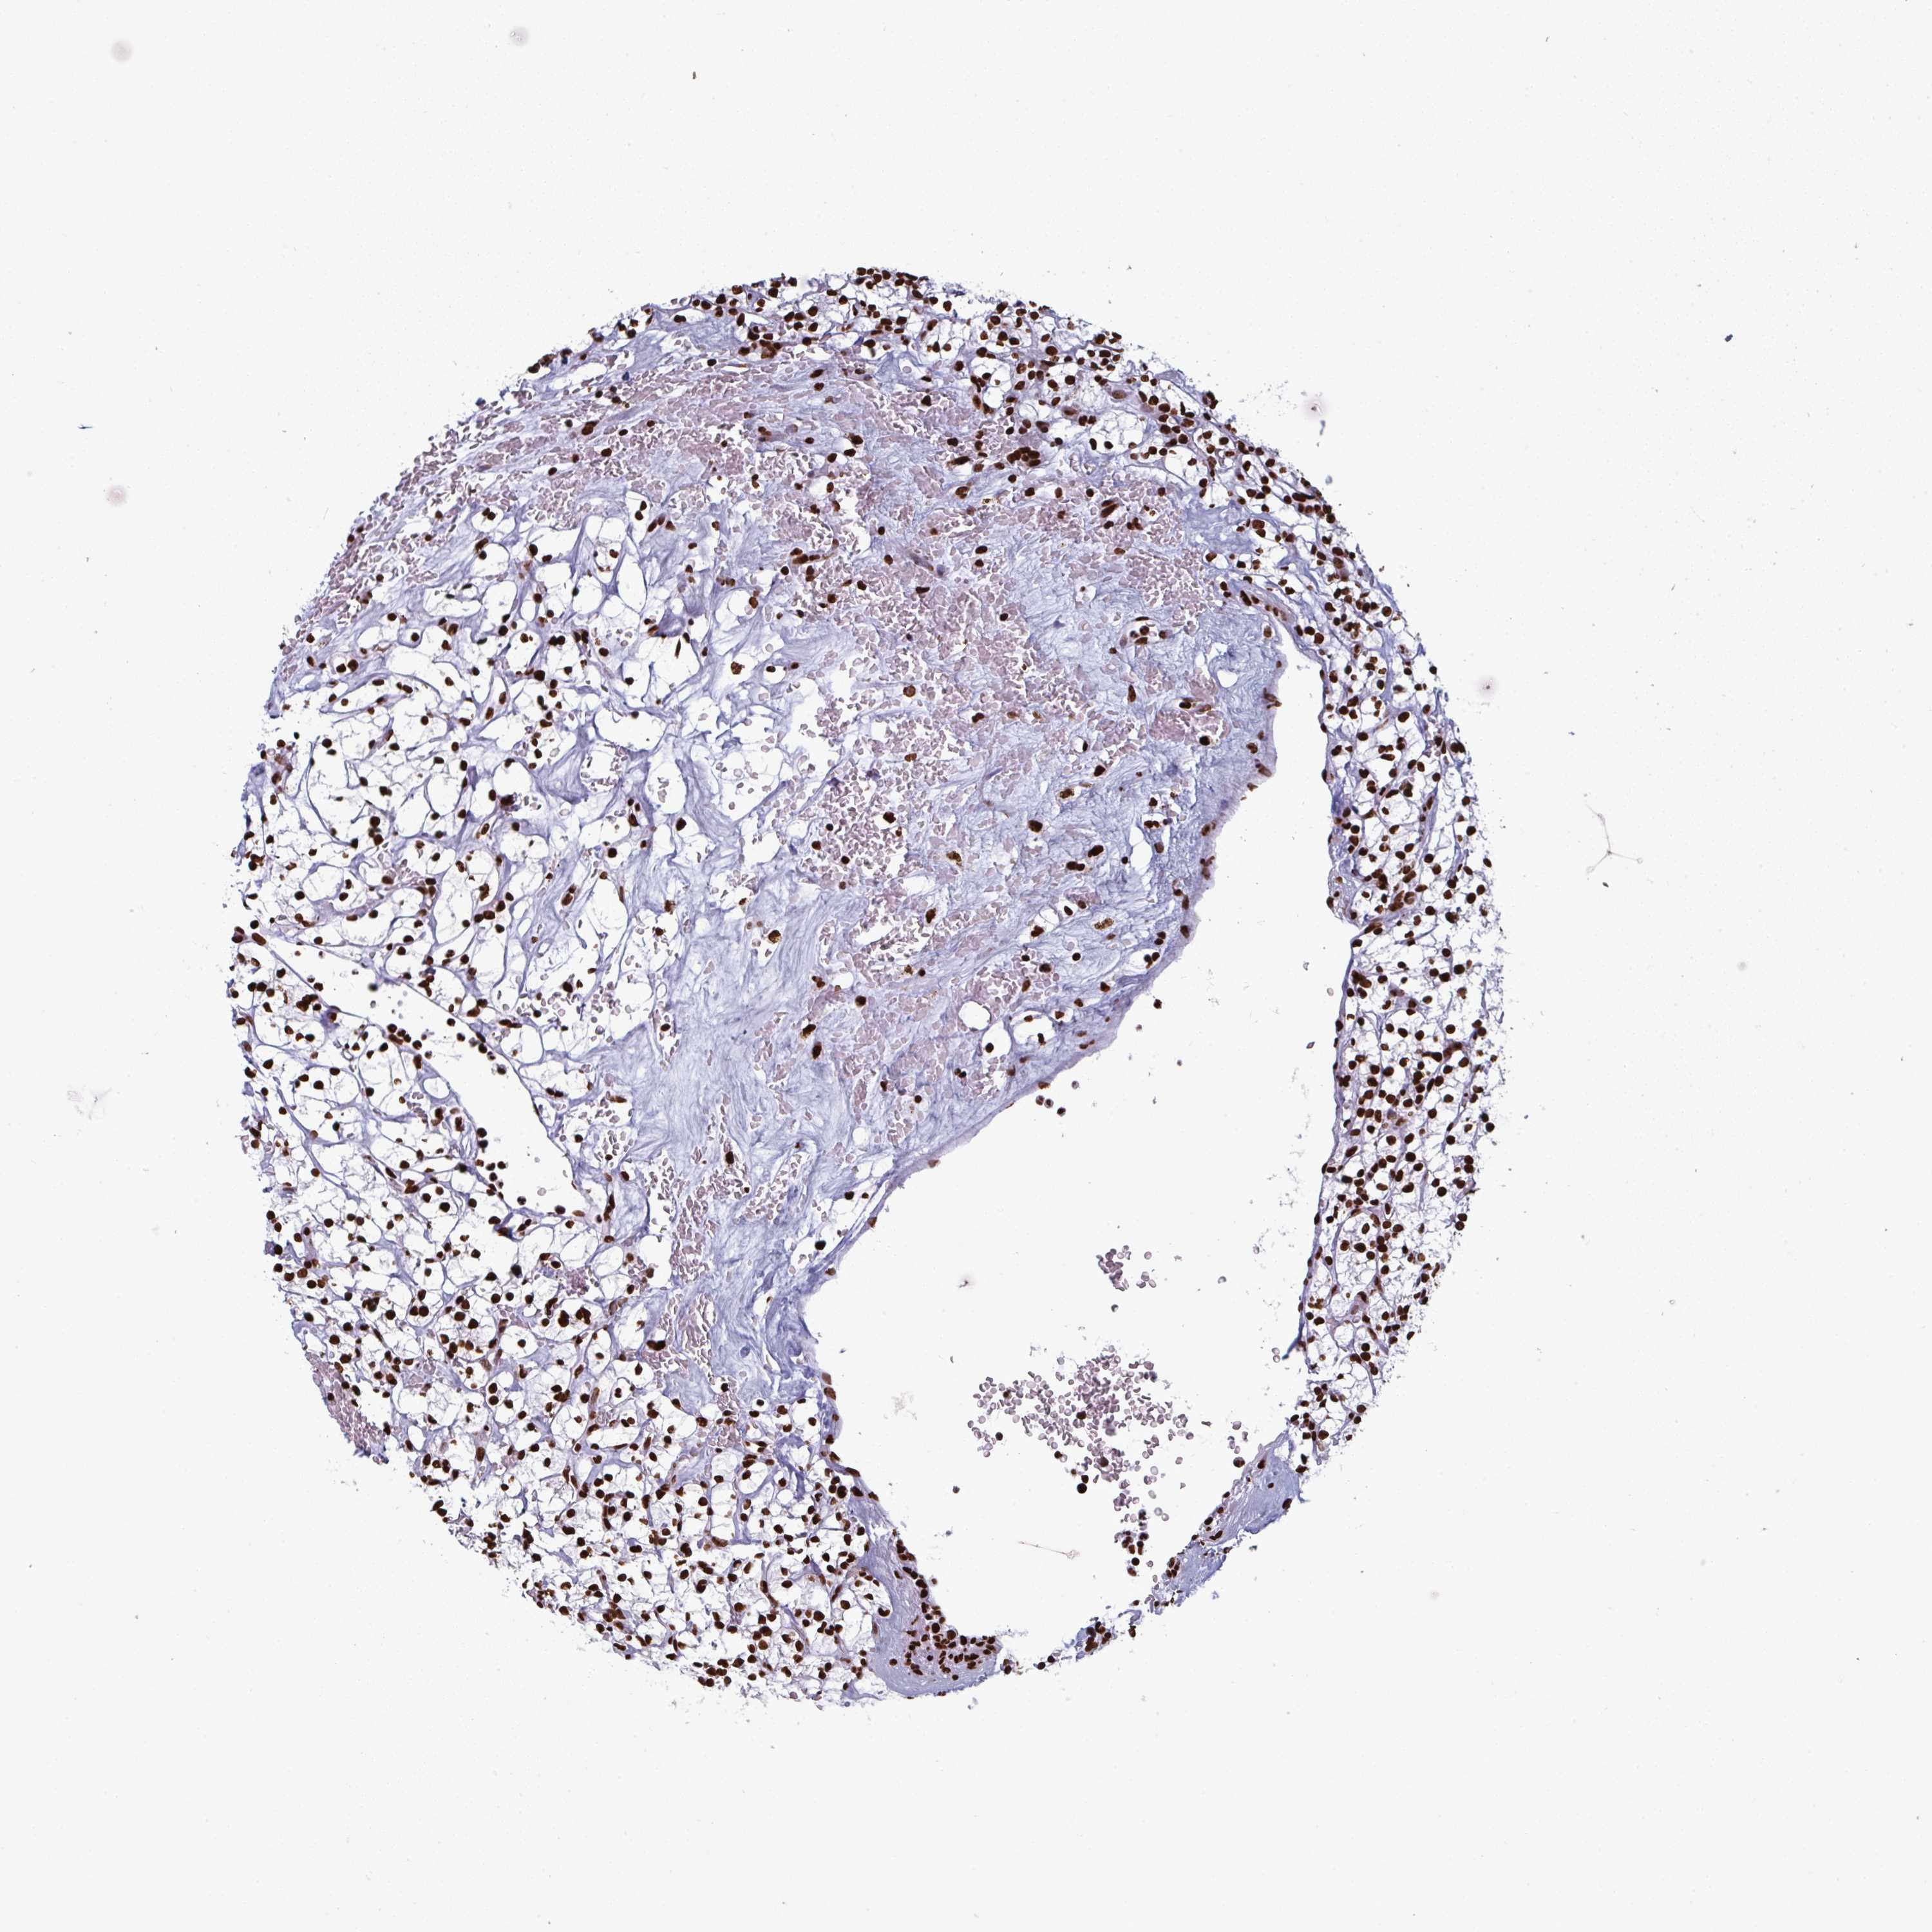

GAR1